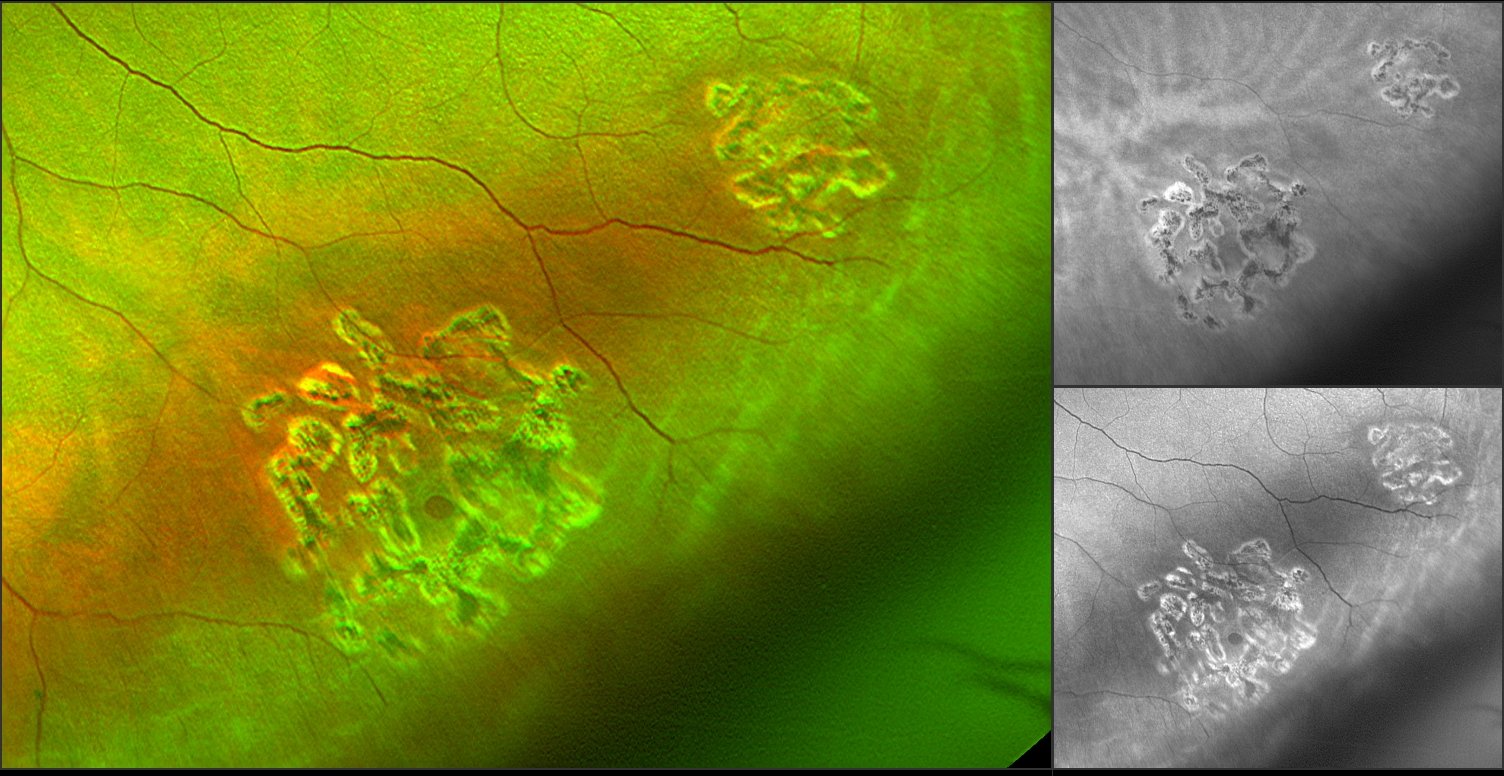

On the first image, the duo spotted a scar that they had never noticed on previous retinal exams. More images with some eye steering and autofluorescence produced an additional two clear retinal holes, and a suspicious spot that served as a guide to target scleral depression. One of the holes was also showing the beginning of a break.

Naturally, Dr. Sclafani went into full doctor mode, she was able to quickly obtain a referral to a retina specialist. The doctor had Liam undergo laser treatment rather than a “watch and wait” approach, and the procedure was successful. Liam is an avid hockey player and his competitive nature did however on more than one occasion result in a few jarring hits to the head. Never enough to cause a concussion, but a contributing factor. Had the couple not performed this exam, this potentially could have led to a retinal detachment. While the initial scar in this case, did not turn out to be a hole, it did spark attention to look in more detail, and began a more serious exam into Liam’s ocular health. Read Liam's whole story here. On the first image, the duo spotted a scar that they had never noticed on previous retinal exams. More images with some eye steering and autofluorescence produced an additional two clear retinal holes, and a suspicious spot that served as a guide to target scleral depression. One of the holes was also showing the beginning of a break.